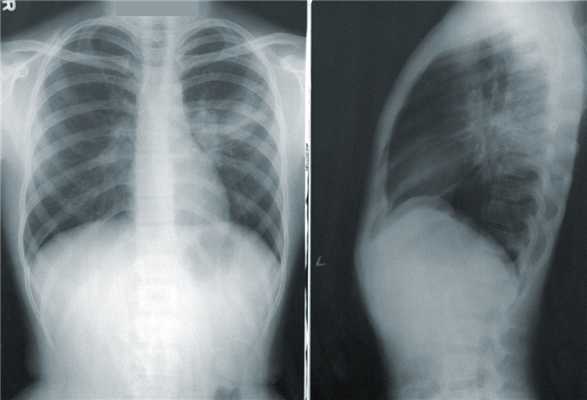

Рентген грудной клетки

Доза рентгеновского облучения при стандартной рентгенографии крайне мала и составляет всего около 0,03 — 0,3 мЗв. Обследование назначается при подозрении на перелом костей (ребер, ключицы), а также если у врача-терапевта или пульмонолога есть подозрения на патологию легких.

Однако разрешающей способности рентгена и двухмерной техники визуализации не всегда достаточно для точной визуальной оценки дыхательного органа. Например, по статистике ВОЗ, выявляемость пневмонии, ассоциированной с вирусом SARS-Cov2, на рентгене всего 50-60%, в то же время на КТ — 95%.